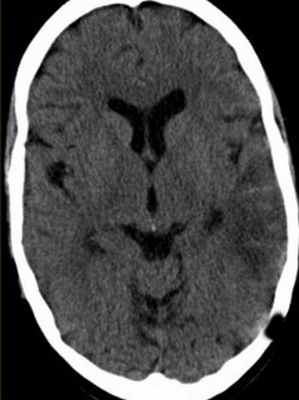

На неконтрастных КТ могут быть видны сгустки крови в тромбированном синусе (“дельта” – симптом), повышенная плотность от синуса (симптом “шнура”). При контрастировании, наоборот наблюдается отсутствие заполнение синуса на ограниченном участке (“обратный дельта” симптом) и отсутствие заполнение синуса контрастом.

прямой “дельта”-знак. КТ, увеличение зоны интереса

КТ с контрастированием. “обратный” дельта-знак.

КТ. Тромбоз вены Лаббе.

КТ. Венозный инфаркт.